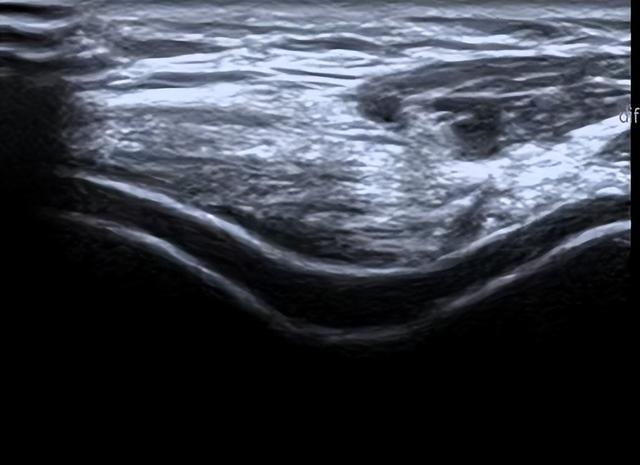

病例2 痛风--软骨损害

▲滑膜增厚、“结晶”形成、关节软骨“双轨征”